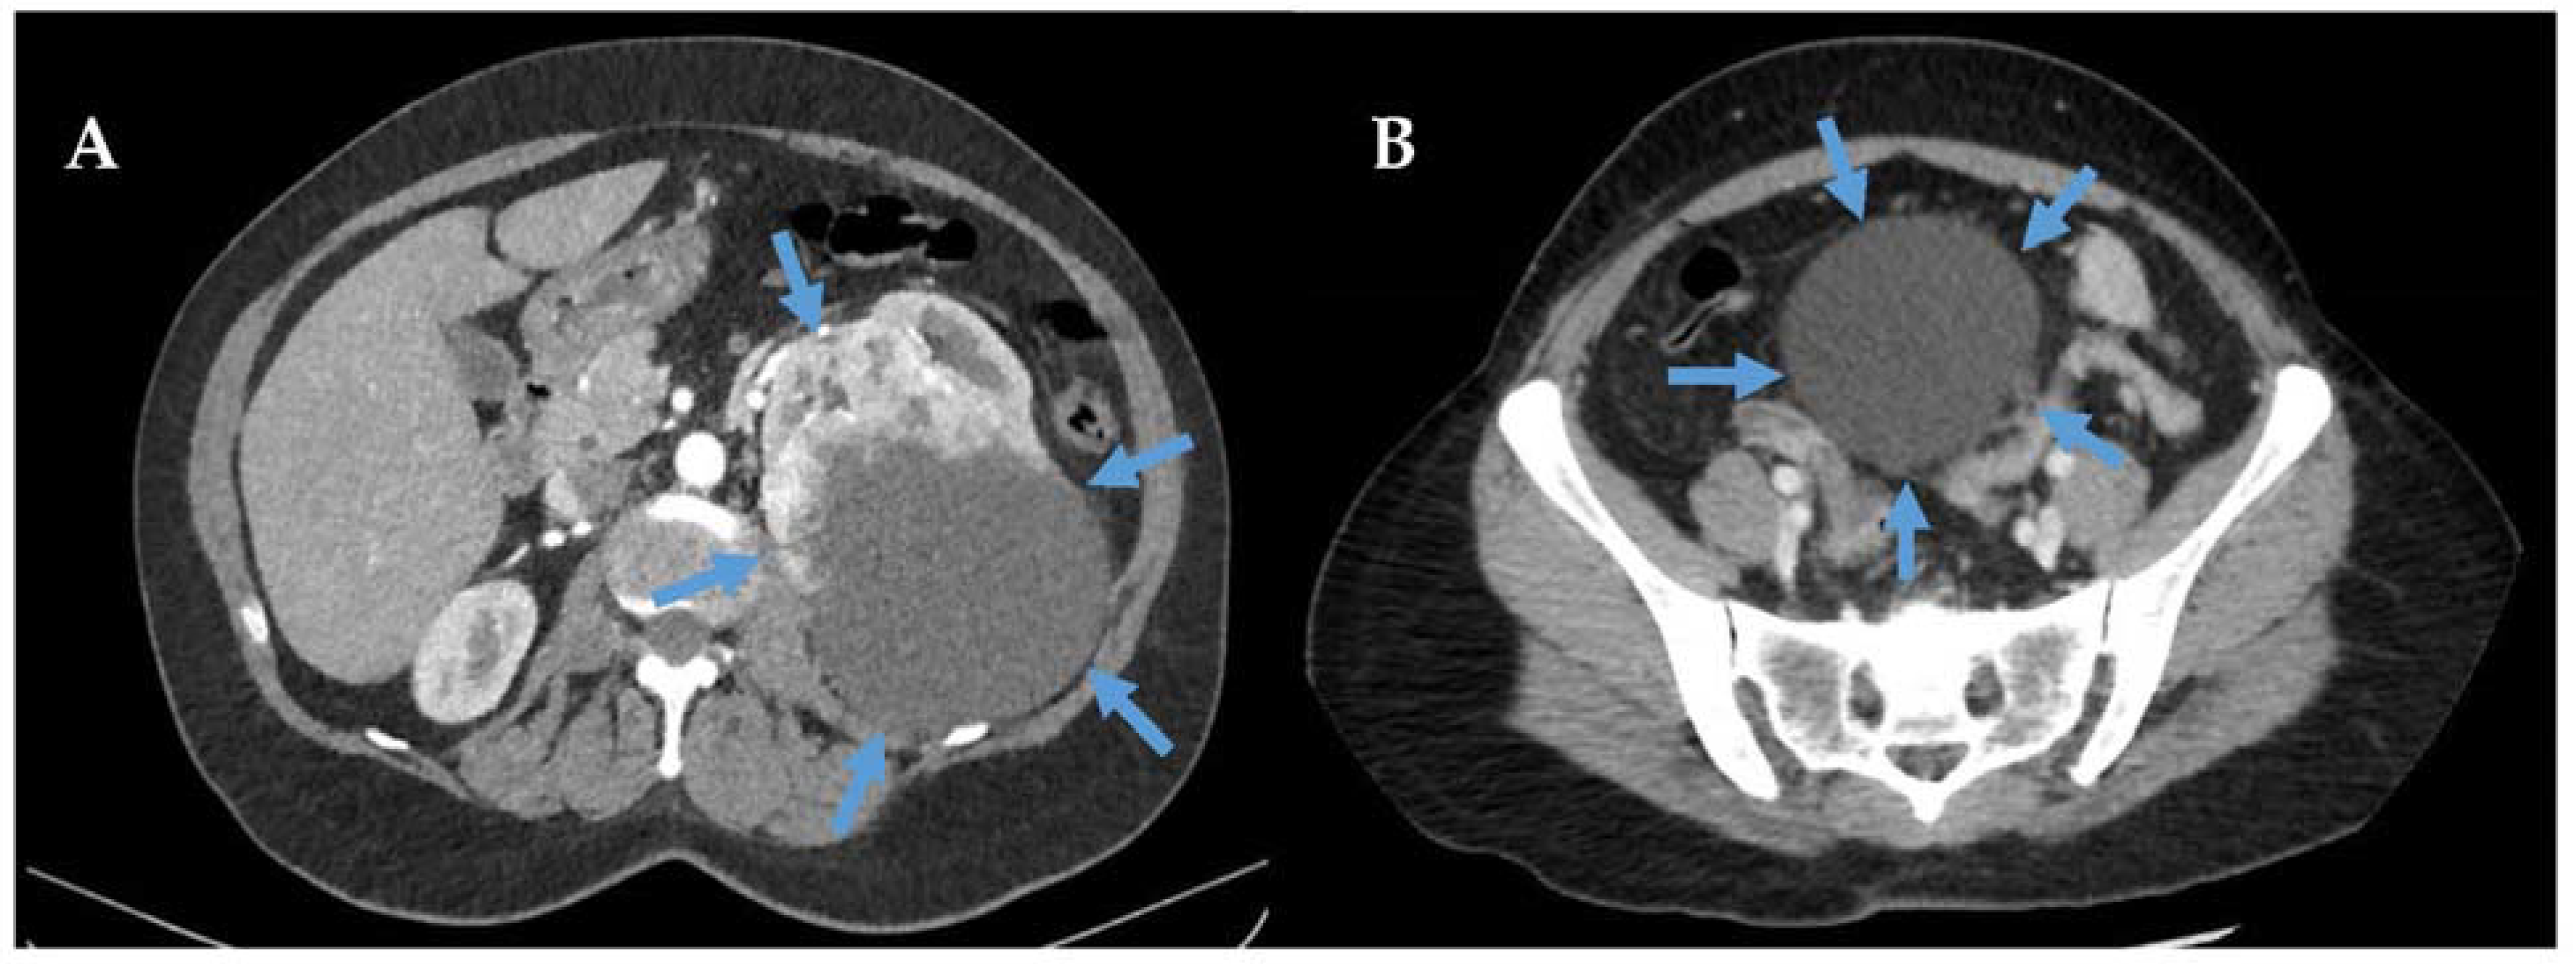

- Yim, H.; Tang, Y.L.; Tandon, A.A. Multifocal Retroperitoneal and Pelvic PEComas Mimicking Liposarcoma: A Case Report and Review of Literature. Radiol. Case Rep. 2021, 16, 2624–2629. [Google Scholar] [CrossRef]